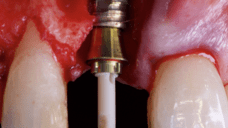

The surgical protocol began with the atraumatic extraction of tooth 1.1 to preserve as much of the alveolar socket as possible. Immediately following extraction, an N1 implant was placed into the socket using a guided surgical approach to ensure ideal three-dimensional positioning. The “one abutment one time” technique was applied to minimize soft tissue manipulation during the healing phase, which is particularly important in esthetic areas.

On the same day as the surgery, an immediate-load provisional crown was delivered. This restoration was fabricated in acrylic resin and screw-retained on the implant, following the “one abutment one time” principle. The provisional crown was carefully adjusted to avoid occlusal loading while supporting the peri-implant soft tissue architecture during the healing phase.